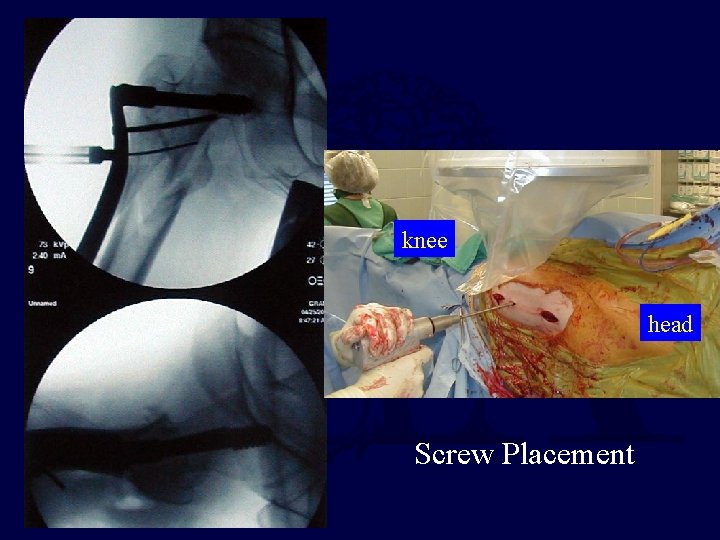

knee head Screw Placement